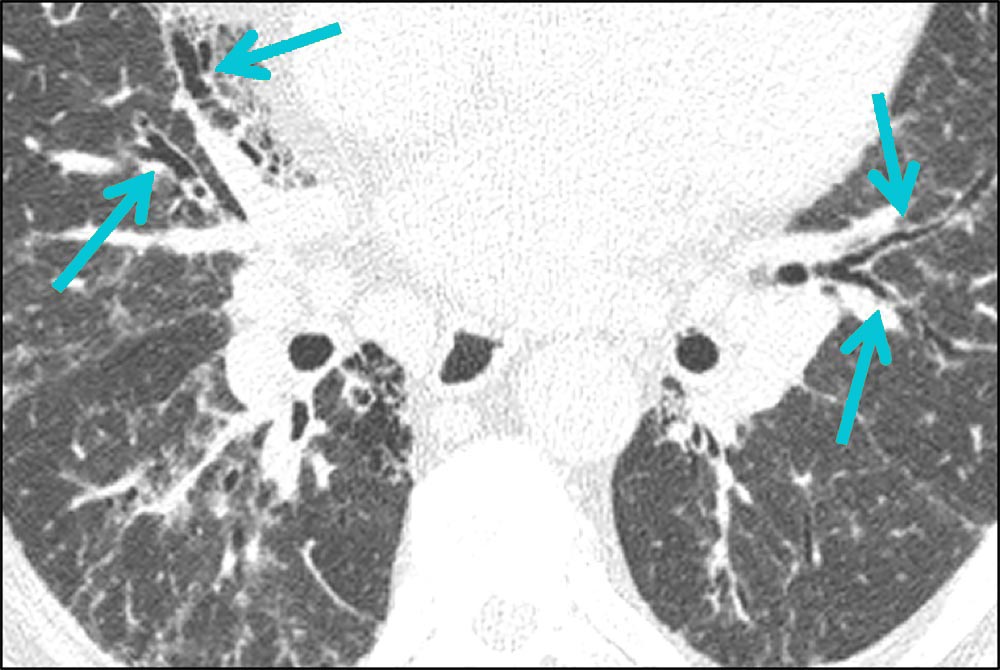

Axial HRCT scan showing prominent traction bronchiectasis, resulting from from fibrotic tissue “pulling” on the bronchi.1 Peripheral, lower-lobe predominant traction bronchiectasis in the setting of changes consistent with fibrosis is highly suggestive of IPF.2,3

Coronal HRCT scan demonstrating traction bronchiectasis.